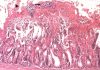

Kolibasilosis merupakan infeksi yang disebabkan oleh E. coli galur virulen yang biasa disebut avian pathogenic Escherichia coli (APEC). Gejala klinis yang terlihat tidak spesifik dan sangat bergantung pada umur ayam yang terserang, akan tetapi umumnya ayam akan terlihat kurus, bulu kusam, nafsu makan menurun, diare, dan ada kotoran yang lengket di sekitar anus. Nafsu makan yang menurun disertai dengan diare otomatis akan mengganggu pertumbuhan. Selain itu, ayam juga akan terlihat sering bergerombol di bawah pemanas.

Infeksi kolibasilosis terbagi menjadi dua, yakni yang bersifat lokal dan sistemik. Bentuk infeksi lokal kolibasilosis dapat berupa omphalitis atau infeksi kantung kuning telur (yolk sac), cellulitis yang biasanya berupa eksudat kental pada jaringan subkutan di bawah kulit (subcutaneous tissue), diare akibat enterotoksin, serta salpingitis atau peradangan saluran telur (oviduct). Sedangkan infkesi sistemik kolibasilosis disebabkan oleh bakteri E. coli yang masuk ke dalam sirkulasi darah dan menyebabkan colicepticemia yang dapat menyebabkan gangguan pada saluran pernapasan hingga peradangan pada selaput otak (meningitis).